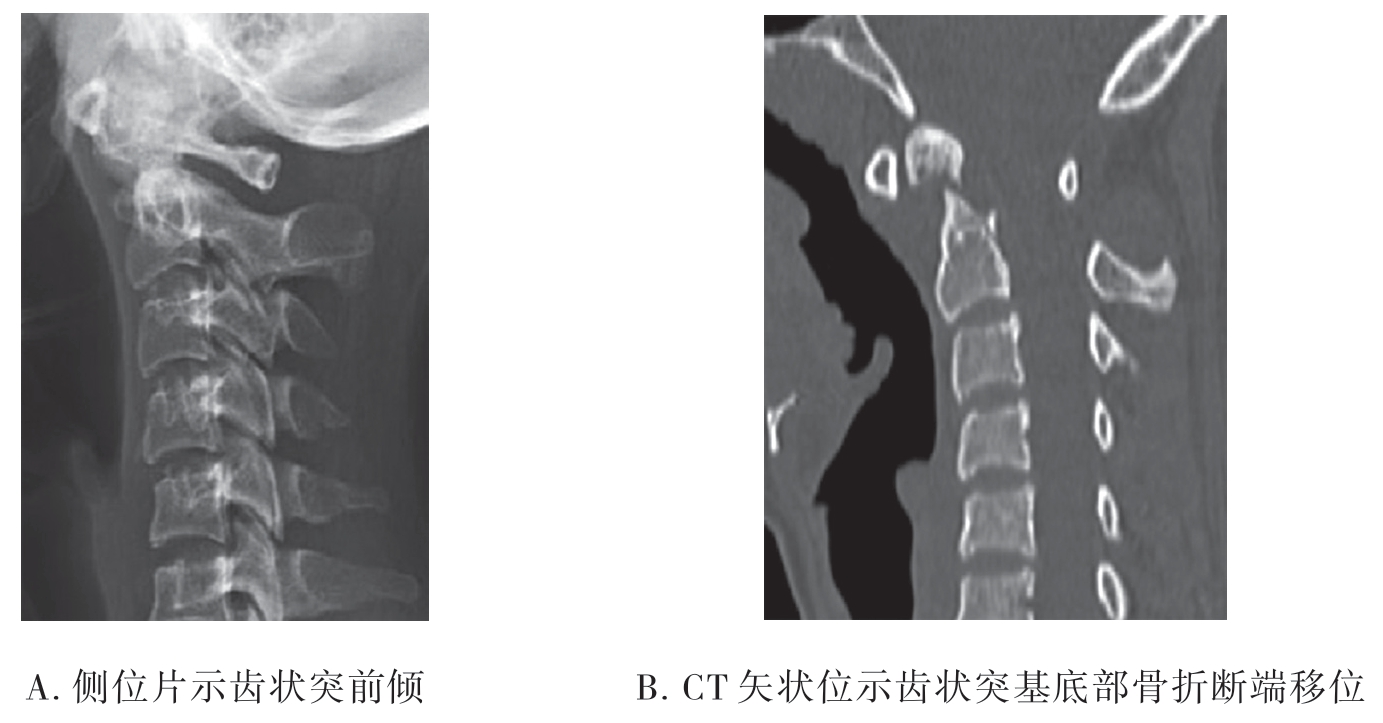

(2)齿状突骨折伴寰椎脱位:伴寰椎前脱位者,侧位片可见齿状突伴随寰椎向前移位(图7-2-11A);伴后脱位者侧位片可见齿状突向后移位。CT检查可清晰显示骨折移位(图7-2-11B)。

图7-2-11 齿状突骨折伴寰椎脱位影像学检查